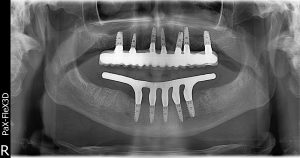

Dental implantology Dr Ehlers is involved in the planning, placement, and exposure of dental implants; immediate implant placement after extraction as well as Customised guides and stents. What is a dental implant? Absent teeth can be replaced by placing titanium implants in the jaw in the area of the absent teeth. A crown or bridge will then be placed on the dental implant. While dental implants may need periodic adjustments, they can last a lifetime when properly placed and cared for over time. A face without teeth can sag and appear sunken and sad. Dental implants allow you to maintain the natural shape of your face and smile. Leaving empty spaces in your mouth after losing one or more teeth can lead to additional health issues, such as the loss and deterioration of some of your jawbone. When it is not being used to support a natural tooth, the jawbone deteriorates, losing its strength and firmness. Dental implants are the only dental restoration option that preserves and stimulates natural bone, actually helping to stimulate bone growth and prevent bone loss. Cavities can’t occur in an implant-restored crown, or replacement tooth; however, you will need to visit your dentist as scheduled and clean and care for it and your gums and mouth every day, the same as you would if it were a natural tooth. It is advised that you have an implant done as soon as possible after having an extraction to ensure bone integrity.